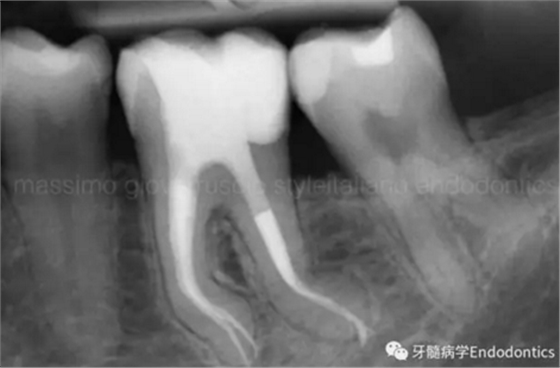

圖6.術(shù)后X線片顯示在根管機(jī)械預(yù)備后保留了原始的根管解剖形態(tài)結(jié)構(gòu)。冠方預(yù)敞和探查保證了對(duì)整個(gè)根管解剖形態(tài)結(jié)構(gòu)的保護(hù)。

圖7.具有解剖障礙的根管,比如根尖區(qū)不規(guī)則的直根管、存在不規(guī)則急彎的彎曲根管。